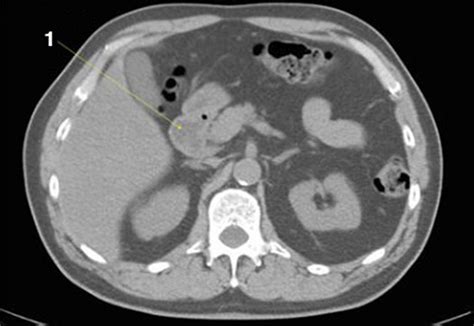

Common Findings in a Normal Abdominal CT Scan

When a Normal Abdominal CT scan is performed, several key findings are expected:

• Clear Organs: The liver, spleen, pancreas, and kidneys should appear clear and free of any masses or cysts.

• Intact Bowel: The intestines should be intact with no signs of inflammation, obstruction, or perforation.

• Normal Vascular Structures: Blood vessels should be clear and free of any blockages or aneurysms.

• No Fluid Accumulation: There should be no abnormal fluid accumulation in the abdominal cavity.